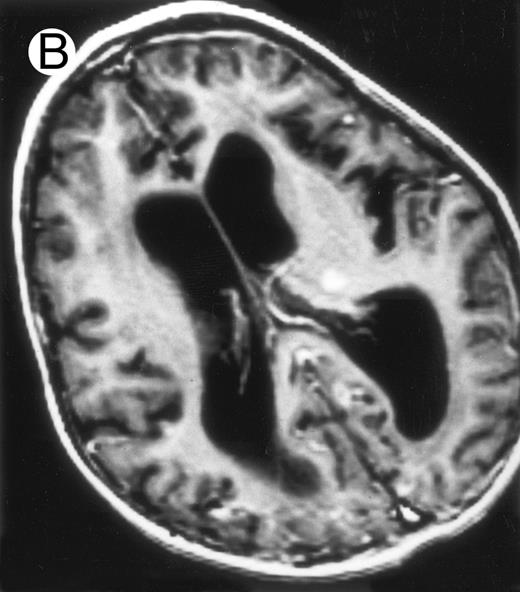

Among the nine children with initial neurological symptoms, seizures were the most frequent initial symptom in the youngest patients, whereas ataxia was found in the two oldest patients (46 and 58 months old, respectively) (Table 1). All nine patients had the same CSF abnormalities as patients with meningitis only. Eight of these nine patients had a neuroradiological study performed at the time of their first neurological symptoms (Table 1). The two most frequent lesions were focal necrosis with parenchymal volume loss and atrophy (Fig 2A and C) and white matter abnormalities (Fig 2B). Several small focal lesions with hypersignal at MR imaging that enhanced after administration of gadopentate dimeglumine (or contrast on CT scan) were also observed in two cases.

Three different aspects of brain imaging in HLH patients. (A) CT scan of a 3-month-old baby showing a large subdural effusion, several necrotic areas and hypodensities of the white matter. (B) Brain magnetic resonance of a 14-month-old boy showing large confluent areas of hypersignal in T2-weighted images. (C) Large symmetrical necrotic areas of cerebellar white matter in a 41/2-year-old girl (MRI).

Together, 19 patients had primary severe CNS disease progression or CNS relapse (Fig 1). Three of 19 had a CNS relapse characterized by meningitis only. Neurological symptoms occurred in 16 of these 19 patients (9 from the onset and 7 after the initial meningitis) (Fig 1). No clinical or neuroradiological difference was detected between the patients who developed neurological symptoms as the initial CNS manifestation or after initial meningitis (Table 1). The occurrence of these neurological manifestations marked a turning point in the evolution of the disease, as chemotherapy led to an improvement of the neurological symptoms in only three patients despite the use of intensive treatment by MTX IT. In these three patients, neurological sequelae persisted after the first symptoms and a relapse occurred within 3 to 10 months. Brain imaging was repeated during chemotherapy for four patients with progression of the CNS disease: in three patients, a severe brain atrophy developed (Fig 3A and B) and in the last patient who initially had contrast enhancement in cerebellar white matter, a cerebellum parenchymal loss was observed (Fig 2C). All of these 19 patients treated by chemotherapy only (n = 15) died during a last episode of coma and brain stem symptoms associated with a systemic hemophagocytic syndrome, 6 ± 6 months after the first neurological symptom (irrespective of the age at this first event). Four of these 19 patients were transplanted (one patient received an HLA-identical BMT, three an HLA-partially identical BMT). Median delay between diagnosis and BMT was 14 months (range, 2 to 20 months). All of these four patients died of BMT-related toxicity and/or disease progression.

Evolution of brain lesions during HLH. (A) MRI of a 41/2-year-old girl showing focal white matter hypersignal on T2-weighted images. (B) MRI of the same child 1 year later with an important atrophy of both the white matter and the cortices.